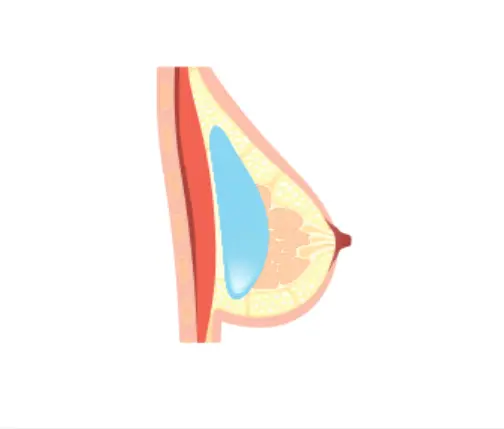

Implant Placement Options

| Placement | Above Muscle | Under Muscle | Dual Plane (Partial Submuscular) |

|---|---|---|---|

| Advantages | – Suitable for sagging or deflated breasts – Natural shape – Less pain and simpler surgery | – Suitable for smaller breasts – Can prevent capsular contracture – More natural result | – For patients with thin skin or low body fat – Reduces implant visibility – Prevents infection – Keeps implant securely in place |

| Disadvantages | – May look unnatural if patient has little fat – Higher risk of capsular contracture | – Slight pain due to tension between muscle and implant – Slightly longer recovery time | – Difficult to position implant if muscles are thick – Risk of muscle tearing or asymmetry |

Above Muscle

Under Muscle

Dual Plane (Partial Submuscular)